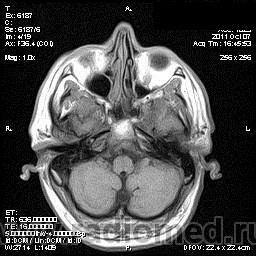

на МРТ - Определяется скопление крови в препонтинной цистерне, в проекции супраселлярной цистерны, в кортикальных бороздах полушарий головного мозга,  в проекции краниоспинального перехода. Выявляется горизонтальный уровень крови в задних рогах боковых желудочков. Боковые, третий желудочки резко расширены. Определяется перивентрикулярное повышение интенсивности сигнала от белого вещества головного мозга. Срединные структуры не смещены. Кортикальные борозды умеренно сглажены. Сильвиев водопровод прослеживается на всем протяжении. Отмечается смещение дна третьего желудочка каудально, с резким уменьшением размеров супраселлярной цистерны; базальные цистерны уменьшены в размере.

В проекции базальной артерии определяется аневризма размером до 4х6 мм.